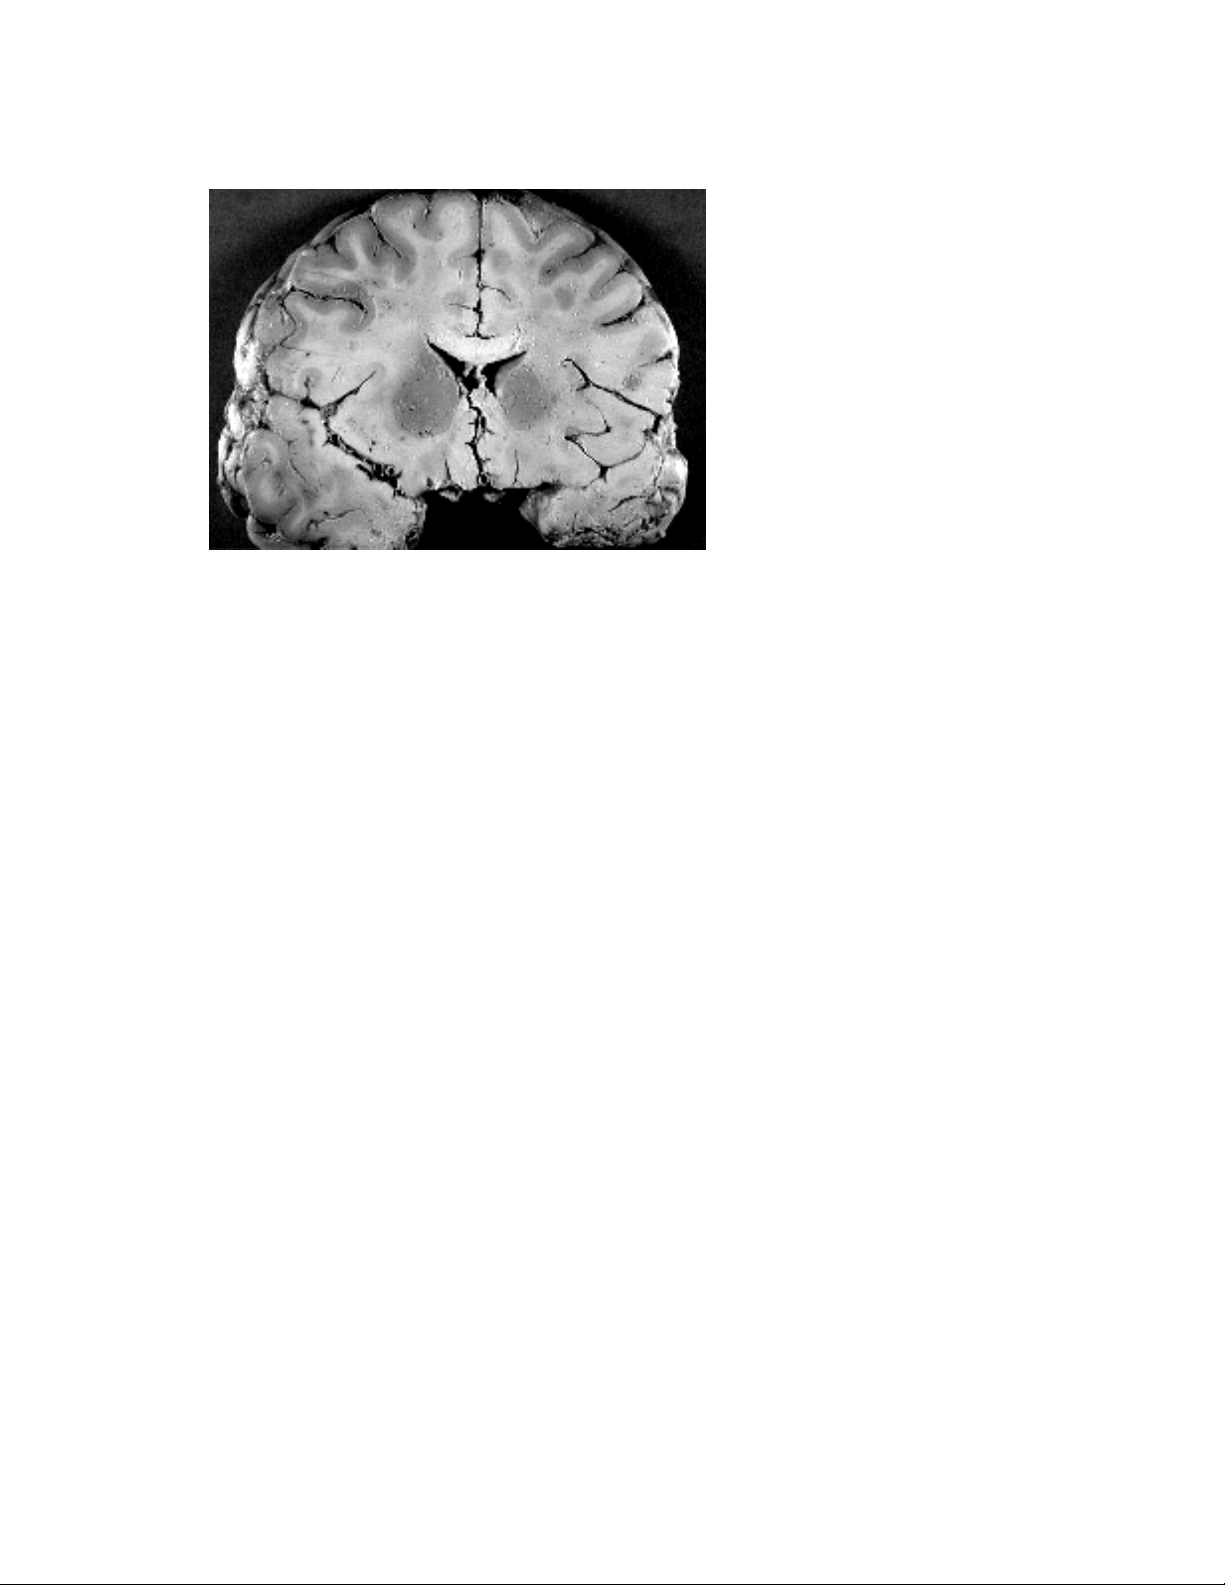

Cấu tạo chung của HTKTW gồm có chất trắng và chất xám, phân bố xung quanh

1 ống. Chất trắng là tập hợp các sợi trục có myêlin, thường kết thành bó; chính thành

phần lipid của myêlin làm cho chất này có màu hơi trắng. Mạch máu trong chất trắng

tương đối ít. Chất xám, có màu xám nhạt khi xem trên não tươi, chứa thân nơron và

sợi thần kinh không myêlin. Phân bố mạch máu tại đây rất phát triển. Chất trắng và

chất xám phân bố khác nhau giữa não bộ và tủy sống. Ở tủy sống, chất xám nằm bên

trong còn chất trắng bao bên ngoài. Ở não bộ thì ngược lại, chất xám tạo thành vỏ

ngoài của đại não, tiểu não và các nhân xám dưới vỏ; chất trắng nằm trong vùng dưới

vỏ.

Ở bán cầu não và tiểu não,

chất xám phủ bên ngoài chất

trắng, tạo thành một lớp được gọi

là vỏ não và vỏ tiểu não. Vỏ não

dày 1,5-4 mm, có cấu trúc thay

đổi tùy theo từng vùng.

Vỏ não bao phủ hai bán cầu

đại não, là nơi phối hợp các cảm giác nhận được, hình thành các đáp ứng vận động

theo ý muốn. Đây là phần não thực hiện các chức năng tư duy từ đơn giản đến phức

tạp, nơi sử dụng ngôn ngữ, học và nhớ. Để thực hiện các chức năng trên, vỏ não phải

rộng, tạo thành các nếp nhăn sâu, gọi là các rãnh. Diện tích chung của vỏ đại não là

2200-2300 cm2, hai phần ba diện tích này nằm sâu trong các rãnh, còn một phần ba

hiện ra ngoài.